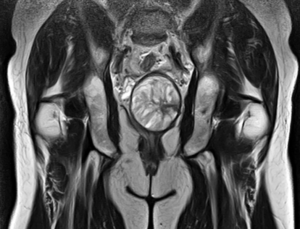

В женском малом тазу расположены внутренние половые органы (матка с придатками, шейка, влагалище), мочевой пузырь и прямая кишка, в мужском — мочевой пузырь, семенные железы, предстательная железа и прямая кишка. Учитывая, что в малом тазу у мужчин и женщин расположены разные органы, показания к назначению МРТ у них также отличаются.

Органы малого таза женщины

Использование МРТ органов малого таза у женщин позволяет выявить патологию женских органов (матка, влагалище, яичники), а также мочевого пузыря и лимфатической системы. С его помощью можно предположить причину основных женских заболеваний: